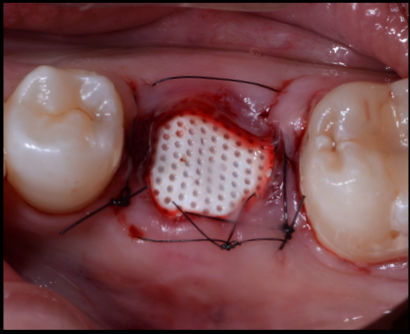

| 治療内容 | 極度の歯科恐怖症で、無痛リラクゼーション治療を希望。 1ヶ月後にカナダに帰るとのことより、それまでに治療を終えてほしい。 左下奥歯は破折を認め、保存が困難な状況であった。他にも治療途中の歯があり、左奥歯がなくなると食事に困るとのことよりブリッジ治療を選択。 本来であれば、抜歯後5ヶ月ぐらいは待つが歯周組織の変化をコントロールするためにソケットプリザベーションと歯肉縁下形成を併用し、即日印象、プロビジョナルレストレーションを調整し、次回アポイント時セットを行なった。 |